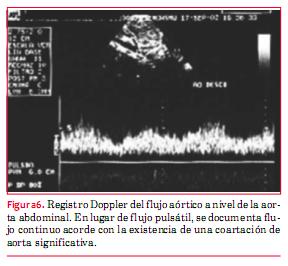

En la coartación de aorta (CoAo) posductal la morfología de la aorta es anormal en forma de S, como puede apreciarse en la figura 4. A este nivel suele observarse flujo turbulento con velocidad aumentada y gradiente que persiste en diástole (“arrastre diastólico”) (figura 5). Finalmente la aorta abdominal carece de expansión sistólica y de flujo pulsátil, registrándose, en cambio, flujo continuo (figura 6). La magnitud del gradiente registrado depende de la importancia de la coartación pero también de la magnitud de la circulación colateral que se haya desarrollado. Un gradiente sistólico máximo de 20 mmHg o superior se considera indicación para actuar sobre la misma (nivel de evidencia C)(15).